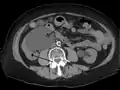

- Stone causing hydronephrosis[14]